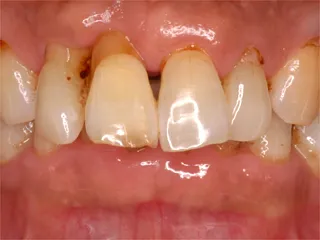

ウォーキングブリーチ 施術前・歯の色が黒っぽくなっています 施術前

ウォーキングブリーチ施術後・自然な歯の白さを取り戻しました 施術後

神経のない歯の漂白です

神経が治療されている歯は年数が経過すると着色することがあります

歯の内部に漂白剤を詰めて歯を白くすることができます

効果には個人差があります